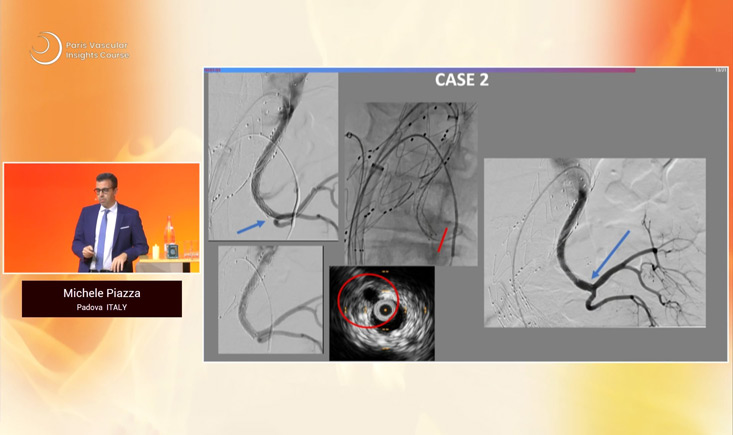

- Compare failure and benefit with IVUS versus angiography during vessel preparation and arterial management

- IVUS assisted septotomy for TBD